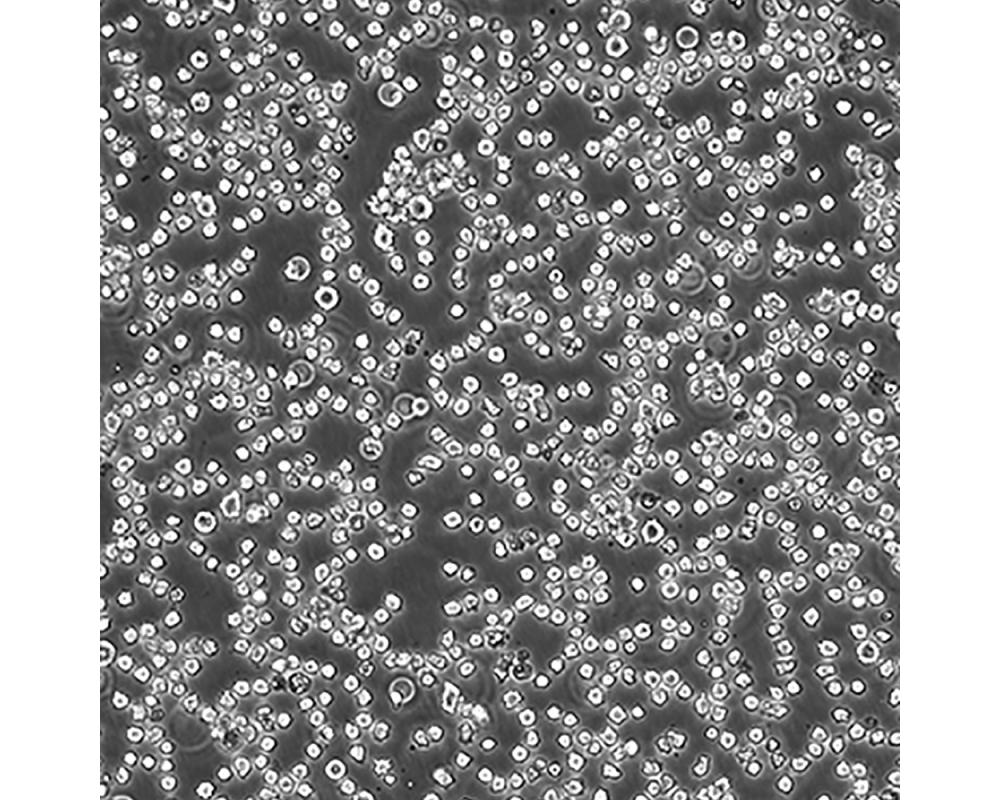

產品名稱 DB

中文名稱 人彌漫性大B細胞淋巴瘤細胞

組織來源 彌漫性大B細胞淋巴瘤;男性

生長特性 懸浮

傳代方法 Maintain cultures at a cell concentraion between between 1 X 10(5) and 1 X 10(6) viable cells/ml.